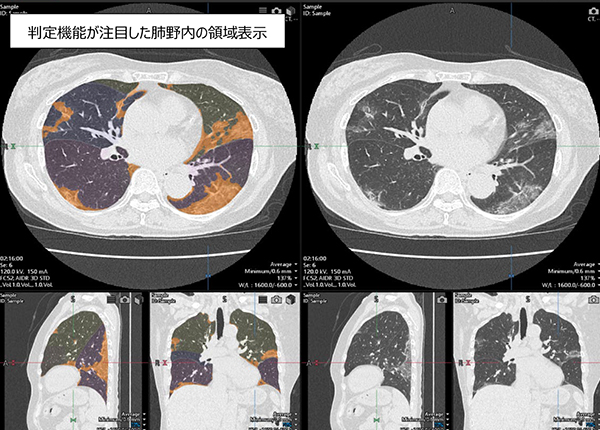

2)COVID-19肺炎像判定機能が注目した肺野内の領域を表示する。

「COVID-19肺炎解析ソフトウェア」の解析結果を表示するワークステーション画面例